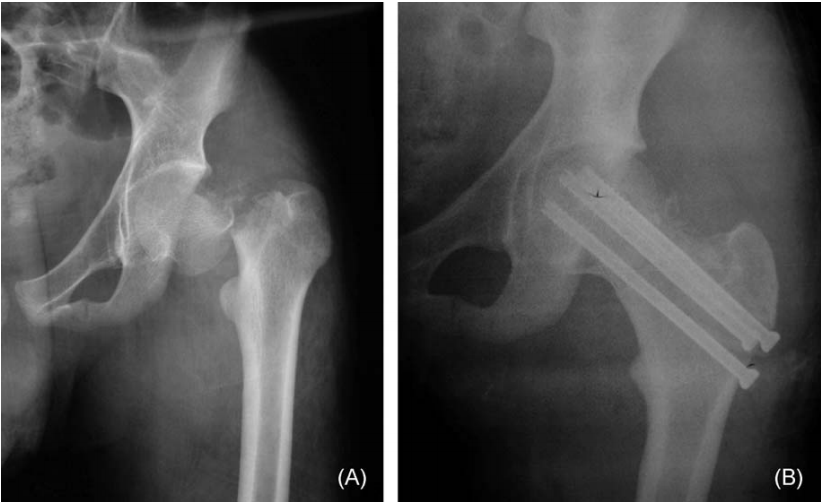

难复性股骨颈骨折定义为在患者全身麻醉下,经过常规闭合复位(如Whitman手法或Leadbetter手法)后难以实现解剖复位的骨折。此类骨折有两种机制。首先,近端骨折块完全与远端股骨分离,成为“浮动”股骨头,使得远端与近端股骨的对线相当困难(图1)。

图 1. 一名15岁男孩因汽车与行人事故导致左股骨颈骨折。前后位X光片(A)显示近端骨折块完全与远端股骨分离,成为“浮动”股骨头,使得远端股骨与近端对线相当困难。采用新技术处理骨折,术后X光片(B)显示解剖复位和牢固固定。